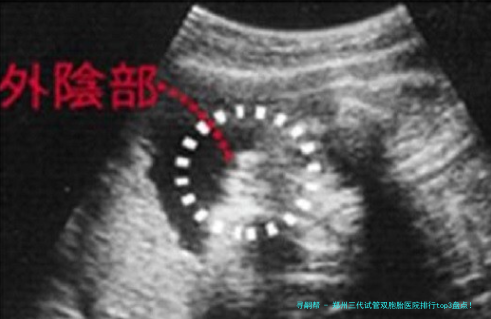

三代试管技术如何科学规划双胎?

很多人好奇:三代试管真正能""孪生儿吗?谜底是:可以科学方案,但不行确保!关键在于胚胎筛选和移植策略

PGT筛查:通过基因学检测检查筛选优质胚胎,提高着床率

双胚胎移植:一次移植两个优质胚胎,增加双胎概率

胚胎体外培养:将胚胎培育至第五日至六日,检查筛选具发育潜能的胚胎